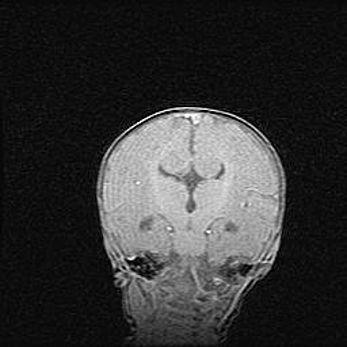

Множественные кисты обоих полушарий головного мозга, наибольшая из них в правой затылочной области. Ассиметричная атрофическая гидроцефалия.

Возраст: 7 месяцев

Вес: 5660 г

Пол: мужской

Окружность головы: 41,5 см

Срок гестации: 28-29 недель

Кисты головного мозга развиваются в результате многоочаговых некрозов вещества мозга и возникают вследствие перенесенной перинатальной инфекции, менингитов, энцефалитов, асфиксии, родовой травмы, расстройств мозгового кровообращения различного генеза. Образованию кист в веществе головного мозга плодов и новорожденных способствуют такие факторы, как высокое содержание в нем воды, недостаточная (или отсутствие) миелинизация и слабая астроглиальная реакция на повреждение.

Кисты могут сочетаться с гидроцефалией и другими поражениями головного мозга.